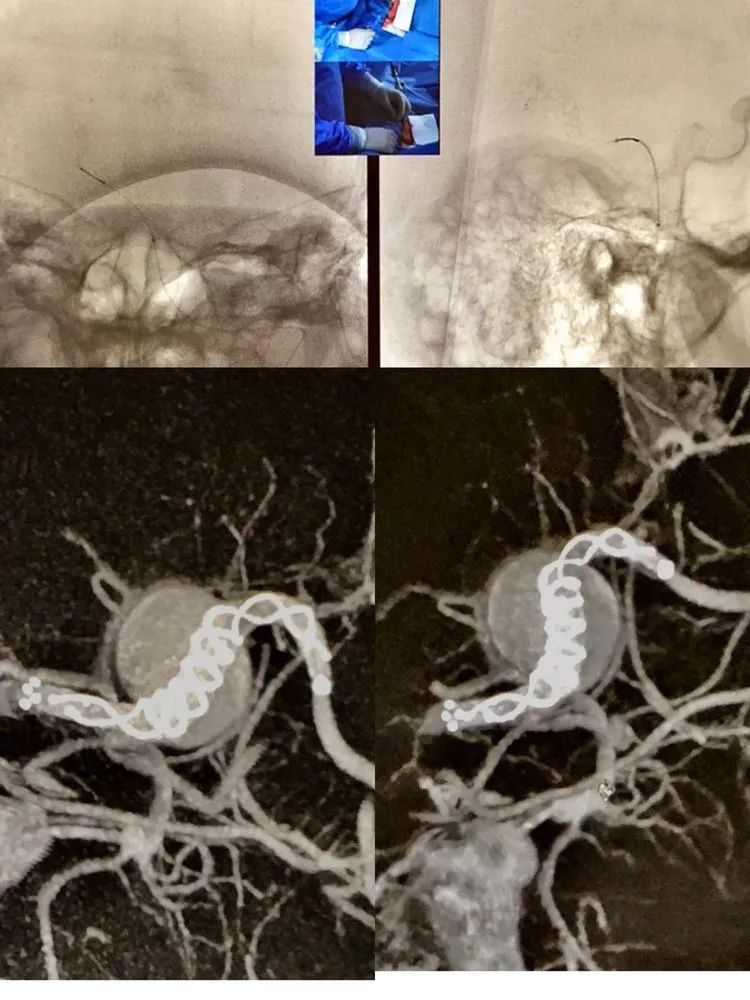

CASE 6 AN

-又是FD ...不评论了

CASE 7 AN

- 对不起,还是FD...趋势啊

-一个下午6台动脉瘤,一个COIL都没有用,血流重构的重要性不言而喻